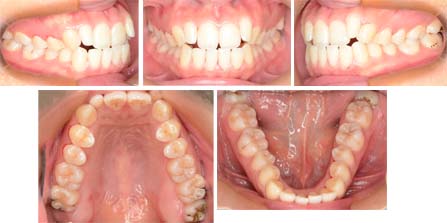

来院時の写真

気になっている点(主訴): 口元の突出 反対咬合

上下前歯が前方に傾斜しています。そのために口もとが出ています。側切歯(上顎前歯の2番目)が小さく円柱状です。リンガルブラケットで治療を開始しました。